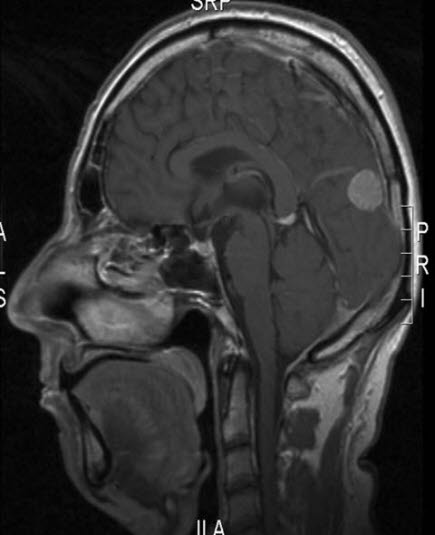

BildeMeningeom, sagittalt snittSist oppdatert: 3. feb. 2016KvalitetssjekkGjengitt med tillatelse av Radiologisk avdeling, Universitetssykehuset Nord-Norge